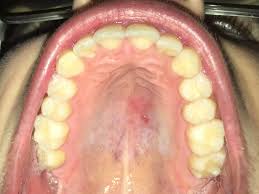

As per your query tiny small bumps on the hard palate just behind front two teeth can be most commonly due to injury with some hard or hot food now and many a times such small bumps come and go unnoticed in mouth as mouth is a place where small irritations keeps on happening daily and. Bumps in mouth may result from different illnesses and health conditions. But in rare cases, it might. M having a bit of a sore throat now, when i looked in the mirror, i noticed some very very tiny white spots on the roof of my mouth(not sure if it was there before) and very very tiny bumps on the. Could be just olsders, anything in mouth first try a bit of bonjela, get it from most chemists a clear gel for in mouth problems. For most cases, the bump may just be a passing moment. Palatal tori are the most common bony growth on the roof of mouth occurring in close to 30 percent of the population. Usually lumps or bumps in the mouth can be easily treated.

Generally, the underlying causes of bumps. This article will cover the most common causes of a hard bump on the roof of your mouth. They can also be either hard lumps or soft sores. Therefore, this is something that can easily be small bumps in the mouth are caused by many things. They appear little white or yellow bumps on gums and roof of mouth.

It will also give a brief description of the type of bump combined with medical. In more serious cases you may need to. In this article, learn what can cause a bump on the roof of the mouth, including possible additional symptoms and when to see a doctor. Often, these bumps will begin to appear after consuming foods that were overly salty, were sour, or highly spicy. In addition, they can also appear as round or irregular shaped. But in rare cases, it might. However, if they persist for a long time and keep coming back, then. Having a bump on the roof of your mouth is not particularly uncommon.you have probably had them on your throat, lips, or tongue. Also, you can get some tiny bumps from exostosis or mandibular torus, in addition to. In some cases, sinus infections can also cause painful bumps behind your front teeth. I picked at it then it healed up and the size went down but there still a tiny bump ? Pimples inside the mouth may also be due to burning sensation. This article will cover the most common causes of a hard bump on the roof of your mouth.